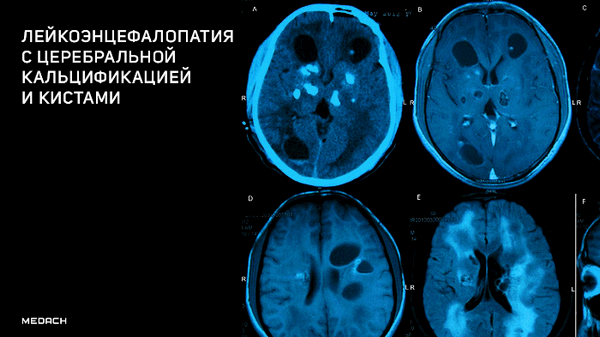

Лейкоэнцефалопатия c церебральной кальцификацией и кистами

Компьютерная томография показала признаки лакунарного черепа (определялись группы круглых, овальных или пальцевидных вдавлений на внутренней поверхности свода черепа, разделенные ребристыми выростами нормальной костной ткани в самых толстых частях лобной, теменной и верхней затылочной костей - характерный признак внутриутробного повышения внутричерепного давления или нарушения костеобразования - прим.пер.), а также обширные области интракраниальных кальцинатов, которые распространялись билатерально на глубокия* ядра мозжечка, границу белого и серого вещества, таламусы, область базальных ядер и капсулы.

а: на топограмме, которая проводится для разметки сканирования, хорошо видны лакунарный череп и интракраниальные кальцинаты.

b: КТ без контрастного усиления показала двусторонние кальцинаты в зубчатом ядре мозжечка;

с: несимметричная двусторонняя обширная кальцификация в области базальных ядер и внутренней капсулы, таламусов и

d: границы серого и белого вещества

На МРТ головного мозга определялись обширные области гиперинтенсивного в Т2ВИ и FLAIR сигнала, которые затрагивали перивентрикулярные области белого вещества, оставляя интактными U-волокна и мозолистое тело с кистозными включениями и признаками обструктивной гидроцефалии. Обнаруженные ранее на КТ кальцинаты были гипоинтенсивны в Т2- и Т1ВИ и показывали «выпадение» МР-сигнала в GRE.

Клиническая и рентгенологическая картины были классическими для лейкоэнцефалопатии с кальцинатами и кистами (LCC, также называемая синдром Лабруна - прим.авт.), которая осложнилась развитием обструктивной гидроцефалии.

На аксиальных Т2ВИ (a, b) и FLAIR (с, d) томограммах можно увидеть обширные области гиперинтенсивности белого вещества мозга, что говорит о лейкоэнцефалопатии.

Аксиальные Т1 и Т2ВИ сканы демонстрируют кисты в обеих гемисферах мозжечка, расположенные над третьим желудочком в пинеальной области; обратите внимание на расширение боковых желудочков в результате обструктивной гидроцефалии.

Области “выпадения” МР-сигнала на GRE в области базальных ядер, таламусов и ядер мозжечка соответствуют кальцинатам.

Сочетание обширных церебральных кальцинатов, изменений белого вещества мозга и кист были описаны Labrune с соавт. в 1996 году под названием LCC. Это крайне редкое состояние, всего в литературе было описано около 10 случаев; оно встречается у детей и взрослых; время появления симптоматики до 59 лет. Классическая для этой патологии клиника прогрессирующего неврологического дефицита у ребенка предполагает огромный список дифференциальных диагнозов, однако существуют характерные рентгенологические признаки, которые позволяют поставить диагноз почти безошибочно.

Данные нейровизуализации тесно связаны с патогенезом. Типично заболевание проявляется двусторонними асимметричными кальцификатами в подкорковых ядрах и ядрах мозжечка, диффузным поражением белого вещества, множественными кистами разного размера с признаками накопления контраста в их стенках, и, изредка, кровотечением в кисты или паренхиму мозга. МР-ангиография обычно без отклонений от нормы, перфузионное исследование определяет гиперперфузию в стенках кист, что вместе с возможными кровотечениями наталкивает на мысль о сосудистых нарушениях.